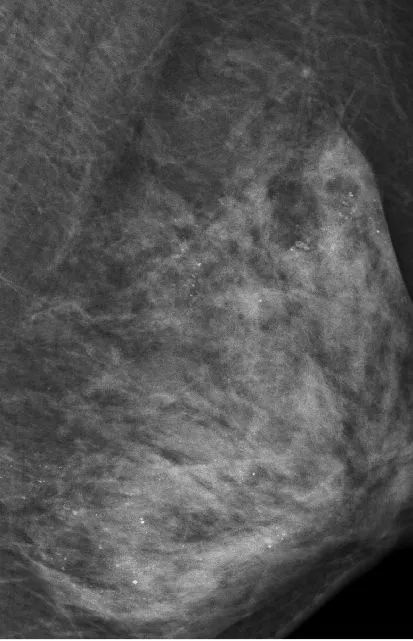

最让医生意外的是她的左侧乳房。乳腺X线检查时,发现里面全部都是细小如沙子一样的钙化灶,布满整个乳腺。

在X光片下,乳腺里满是星星点点的钙化灶

让管床医生陶龙犯难的是,如此多的细小钙化灶,无法判断哪些是良性哪些是恶性。

乳腺沙砾样钙化灶是乳癌的信号之一,需要高度关注。